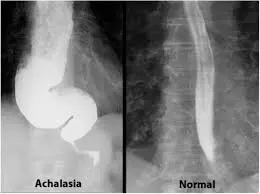

1. فحص الباريوم

يُعد فحص الباريوم من أهم الفحوصات التشخيصية. يبتلع المريض مادة الباريوم، ثم يتم تصوير المريء بالأشعة السينية لرصد حركة المادة وتحديد مواضع الانسداد أو الضيق.